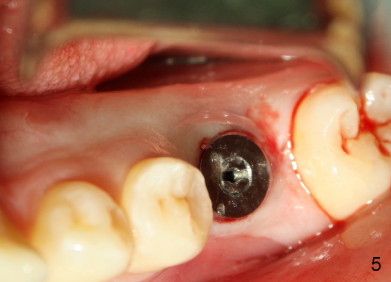

A 22-year-old man requested extraction of the tooth #19 (Fig.1).  X-ray was taken 3 and 8 months post extraction, respectively (Fig.2,3).  A 6x17 mm Tatum tapered implant was placed (Fig.4,5). A 5 mm (in diameter) 0 degree unipost (5 mm in height) was prepared 7 months after implant placement. Due to limited space, time was spent for extraoral and intraoral reduction of the abutment.